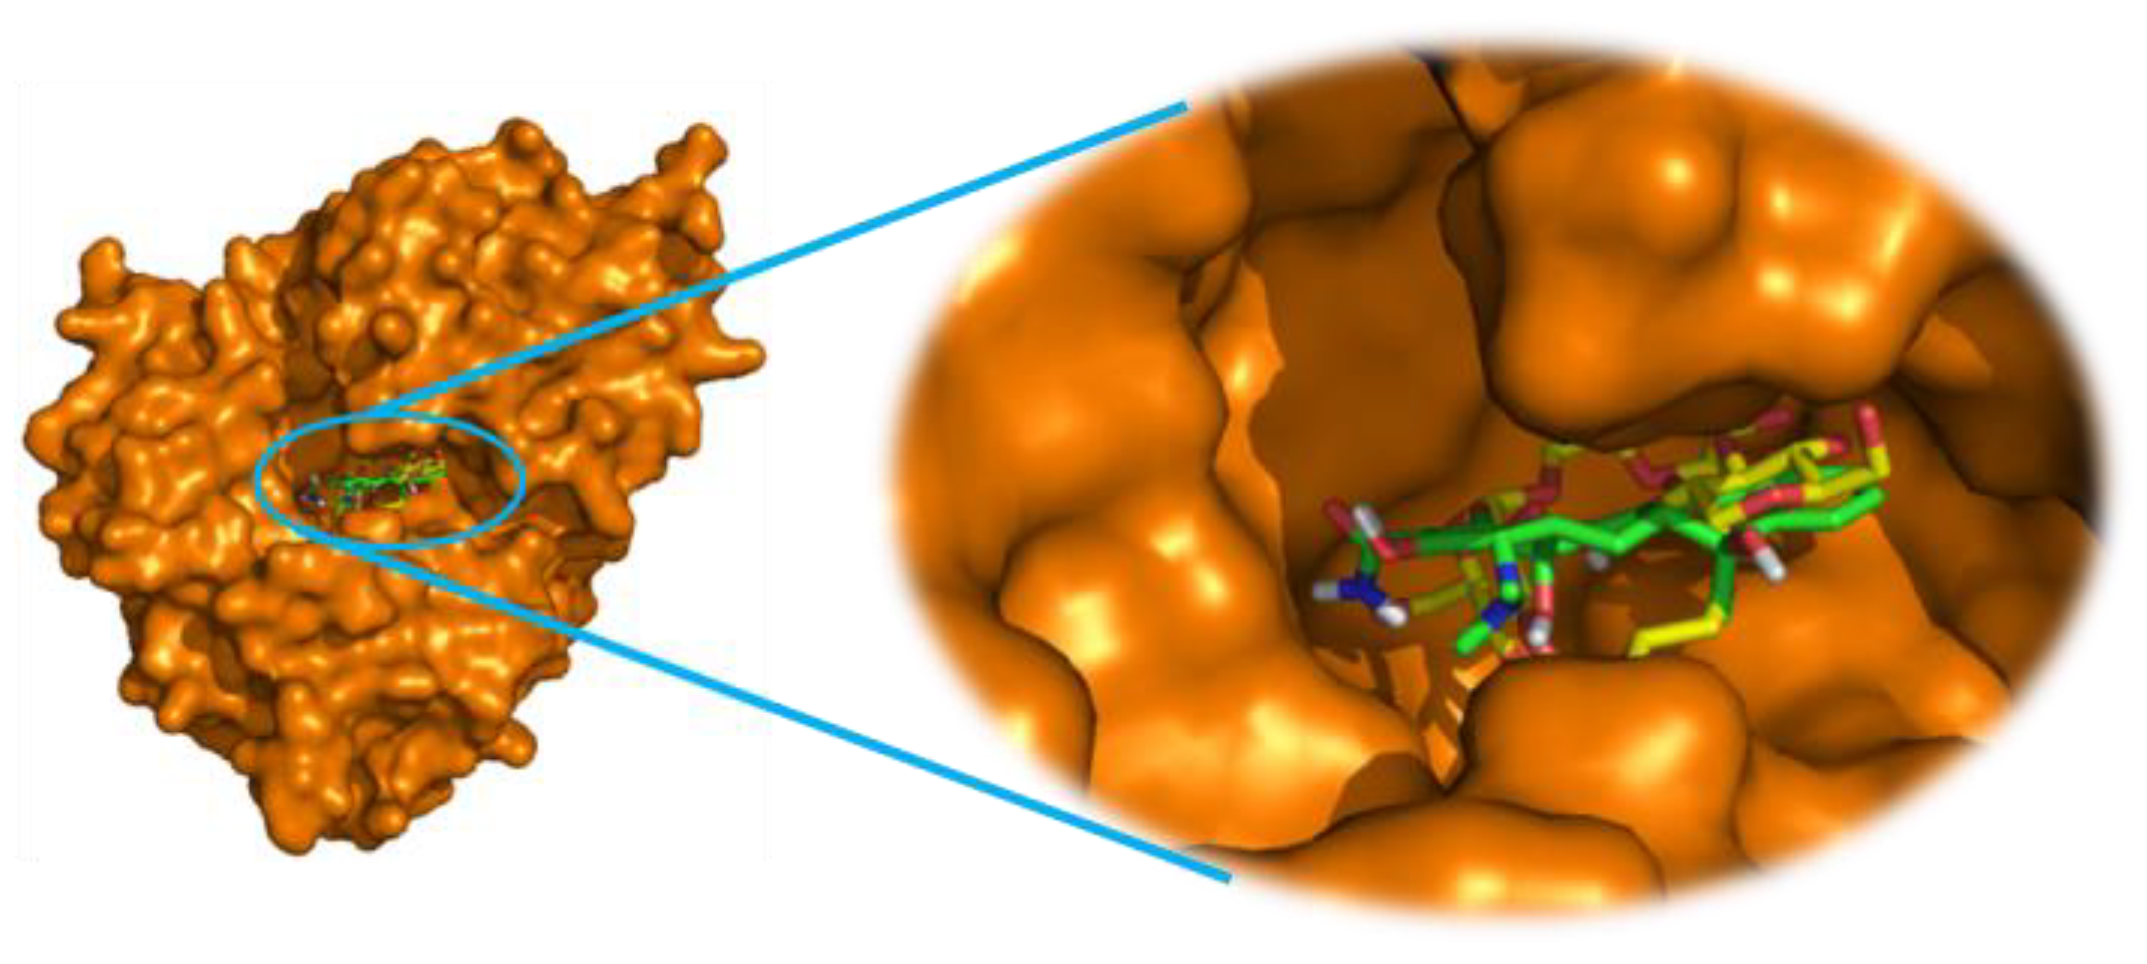

2.3. Molecular Docking Study

3.4. Molecular Docking Procedure